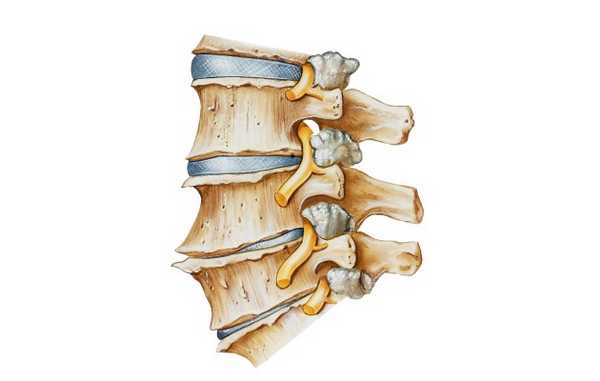

Дата публикации: 16 Июня 2021 года

Каждый позвонок, принимающий участие в построении осевого скелета, имеет 7 отростков: 1 непарный (остистый) и 6 парных (2 поперечных, 2 верхних и 2 нижних суставных). Именно посредством этих костных выростов позвонки соединяются друг с другом, образуя дугоотросчатые суставы.

Позвоночный столб состоит из 31-34 позвонков. При этом 24 позвонка соединяются между собой с помощью подвижных сочленений, а остальные срастаются и образуют две кости: крестец и копчик. Каждый позвонок образован лежащим впереди массивным телом и расположенной сзади дугой. Дуги позвонков являются вместилищем для спинного мозга. У каждого позвонка, кроме I и II шейного, есть семь отростков: один остистый, два поперечных, два верхних и два нижних суставных.

Между телами позвонков расположены эластичные межпозвонковые диски, а верхние и нижние суставные отростки соседних позвонков соединены при помощи суставов. Кроме того, позвоночный столб укреплен связками: задней, передней, надостистыми, межостистыми и междужковыми (желтыми). Такая конструкция обеспечивает оптимальное сочетание стабильности и подвижности, а межпозвонковые диски амортизируют нагрузки на позвоночник. I и II шейные позвонки имеют вид колец. Второй позвонок снабжен зубовидным отростком - своеобразной осью, на которой голова вместе с первым позвонком вращается относительно туловища.